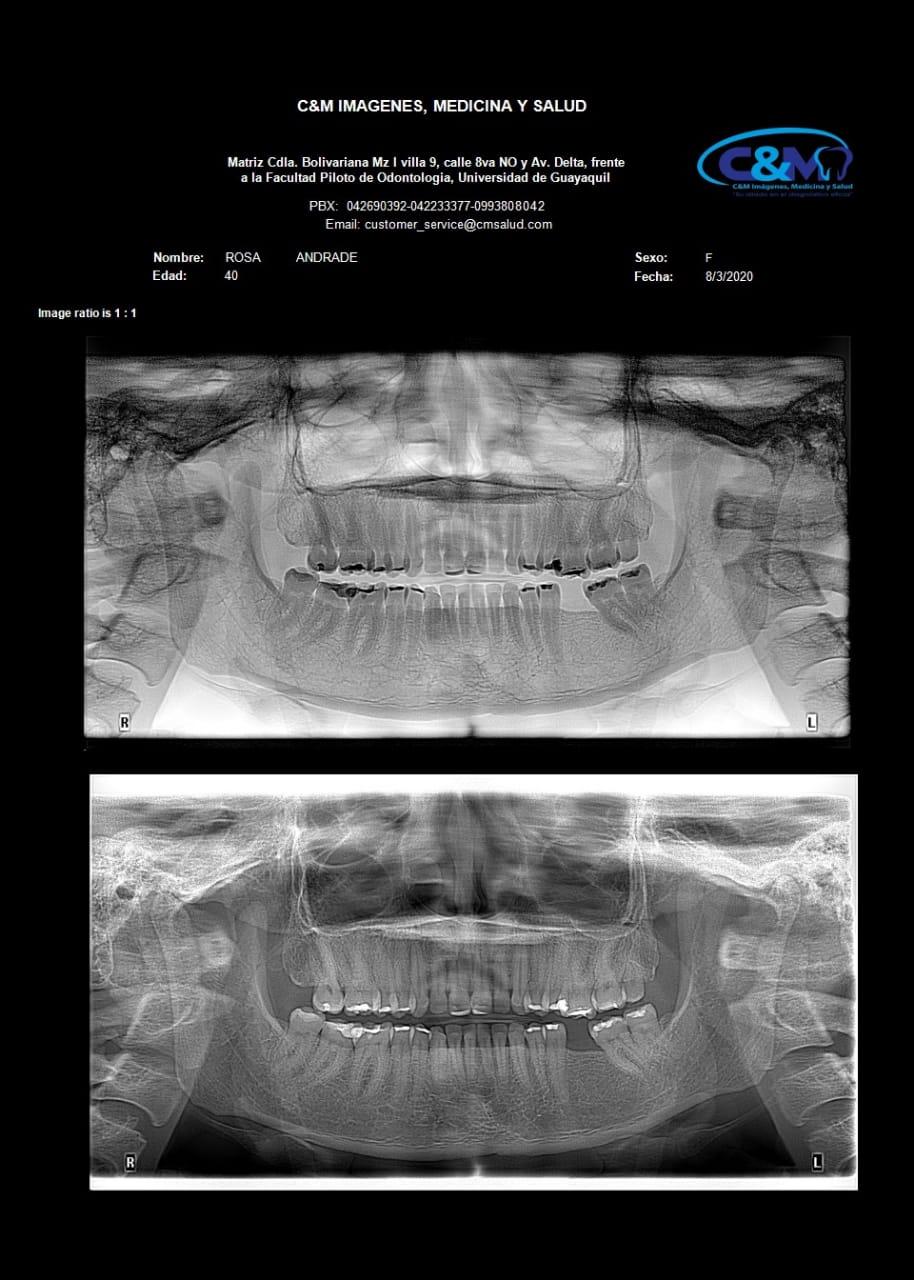

ESPECIFICACIONESPanoramica plus (invertir el contraste ) podemos observar mejor las estructuras dentarias y osea de esta radiografia

PANORAMICA

ESPECIFICACIONESLa radiografía panorámica es una técnica radiológica que muestra las estructuras óseas (los maxilares, la articulación de la mandíbula y los dientes) en una sola imagen general.